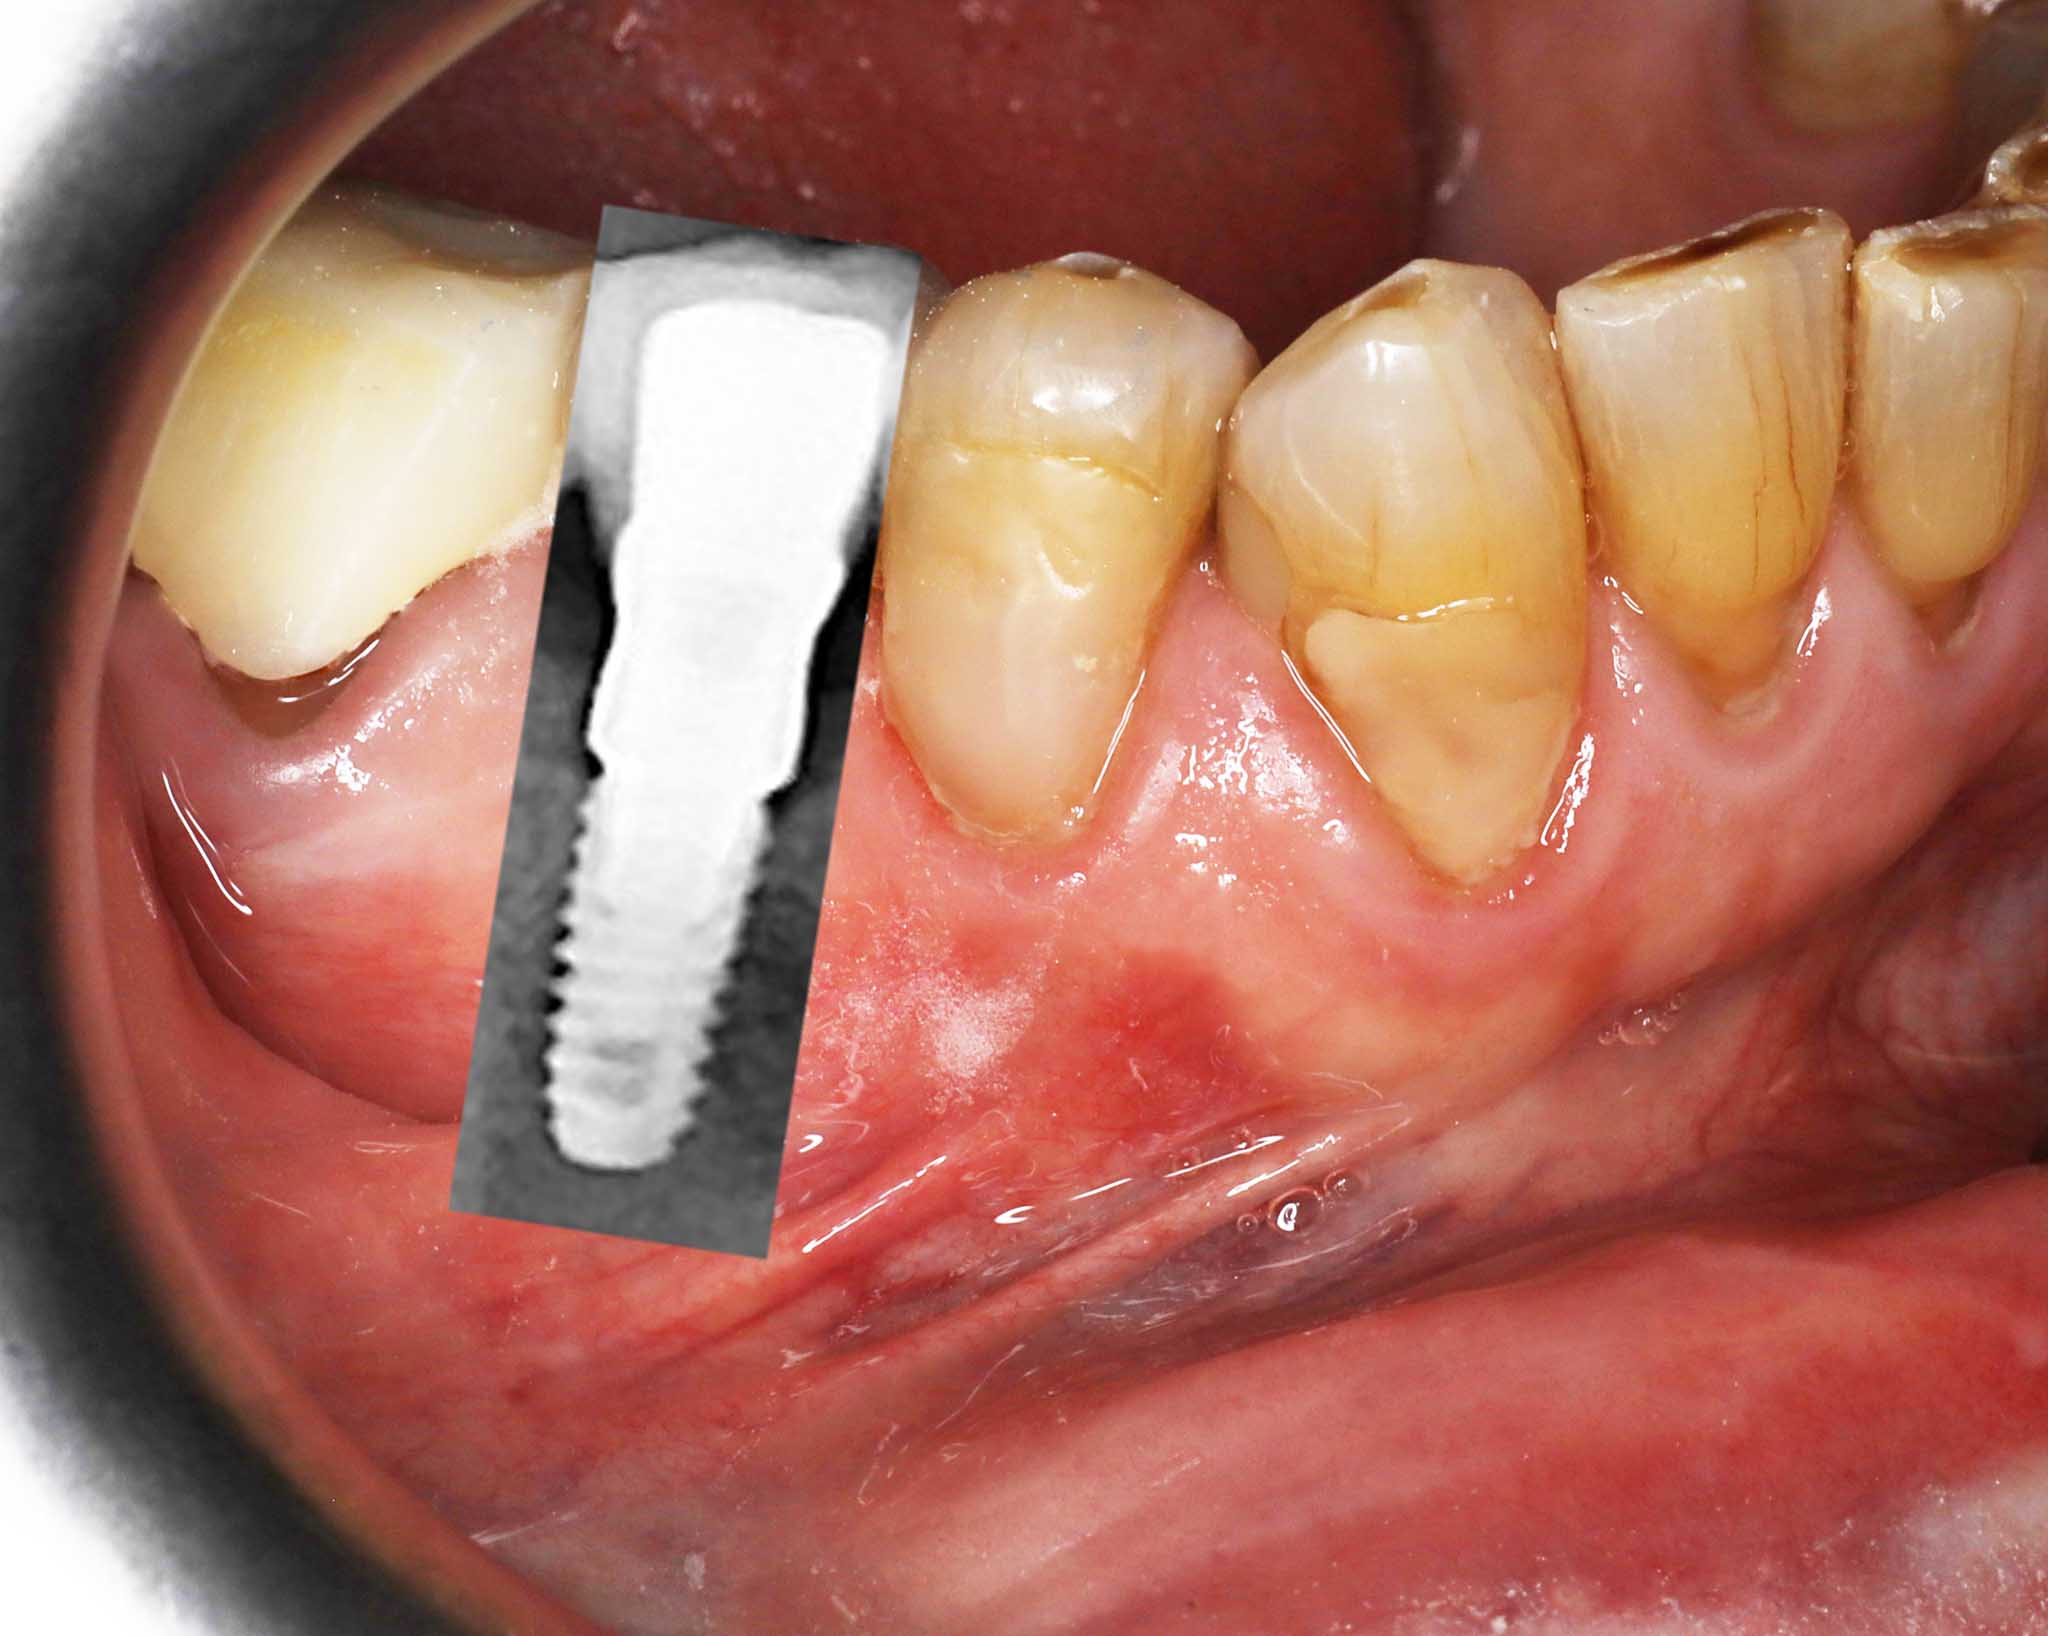

Et tannimplantat er en kunstig tannerstatning som likner mest i struktur på en ordinær tann. Et tannimplantat består hovedsakelig av to deler

- en kjevedel som forankres i kjevebenet (også kjent som fikstur)

- en tyggedel som festes over kjevedelen (navn avhengig av løsning).

Kjevedelen har form som en skrue, med gjenger, men uten en spiss tupp. Kjevedelen settes i kjevebenet, hvortil kjevebenet rundt vil vokse inn til denne og omsider forankre den. Når kjevedelen er klar til å belastes, festes tyggedelen til kjevedelen. Det finnes forskjellige tyggedeler som kan festes til kjevedelen, og disse skal vi introdusere lengre ned.

Før- og etterbilder av tannimplantater – Se våre pasientresultater

Flere bilder